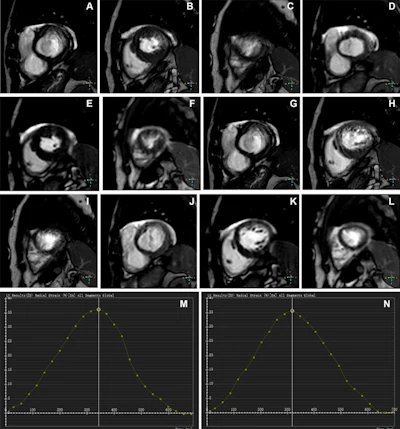

Representative images of participants with difficulty with breath holding and arrhythmia. In the lower right corner of A–L, the position coordinates of the images are marked. Short-axis (SA) view images in the end-systole (A–F) and end-diastole (G–L) phases in participants with atrial fibrillation. (A–C, G–I) Balanced steady-state free precession (bSSFP) cardiac cine. (D–F, J–L) Deep learning–enhanced compressed sensing (AI-CS) single-shot cardiac cine. In contrast to AI-CS single-shot cardiac cine, endocardial contours were challenging to identify on conventional segmented cine in midventricular and apical sections. (M) Line graph of time curve during the whole cardiac cycle obtained from bSSFP cardiac cine. (N) Line graph of time curve during the whole cardiac cycle obtained from AI-CS single-shot cardiac cine. LV = left ventricle; 2D = two-dimensional.RSNA

The researchers measured left ventricular volumetric and strain parameters measured by both methods; parameters included end-diastolic volume, end-systolic volume, stroke volume, ejection fraction, peak strain (in radial, longitudinal, and circumferential directions), and standard deviation of peak strain. Three cardiovascular radiologists analyzed the images, assessing artifacts and the visibility of cardiac structures. These readers were blinded to clinical information and prior imaging results.

- The AI-CS single-shot cine showed better image quality compared to conventional cine, particularly in participants with arrhythmia, with fewer "mistrigger" events (when the scanner misses an intended phase due to the patient's irregular heartbeat) and motion artifacts.